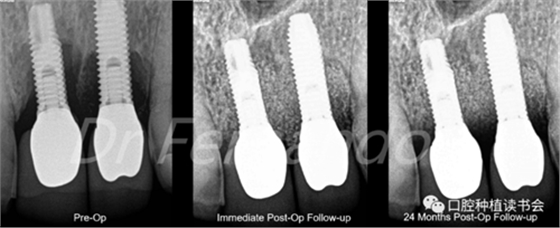

盡管手術治療似乎能改善結果;但只有將手術治療和骨再生相結合才能獲得更高的成功率。Schwarz等人發(fā)現(xiàn)這種再生手術治療有2年以上的滿意效果,能使種植體周圍的骨吸收停止,探診出血率由80%降至34%(圖5 )。

圖5通過手術治療,種植體周圍獲得骨再生,術后2年效果穩(wěn)定(圖2、圖4相同病例)